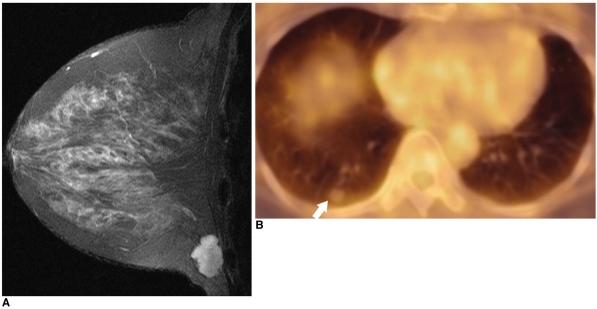

Fluorodeoxyglucose (FDG)-positron emission tomography (PET) is being used more and more to differentiate benign from malignant focal lesions and it has been shown to be more efficacious than conventional chest computed tomography (CT). However, FDG is not a cancer-specific agent, and false positive findings in benign diseases have been reported. Infectious diseases (mycobacterial, fungal, bacterial infection), sarcoidosis, radiation pneumonitis and post-operative surgical conditions have shown intense uptake on PET scan. On the other hand, tumors with low glycolytic activity such as adenomas, bronchioloalveolar carcinomas, carcinoid tumors, low grade lymphomas and small sized tumors have revealed false negative findings on PET scan. Furthermore, in diseases located near the physiologic uptake sites (heart, bladder, kidney, and liver), FDG-PET should be complemented with other imaging modalities to confirm results and to minimize false negative findings. Familiarity with these false positive and negative findings will help radiologists interpret PET scans more accurately and also will help to determine the significance of the findings. In this review, we illustrate false positive and negative findings of PET scan in a variety of diseases.